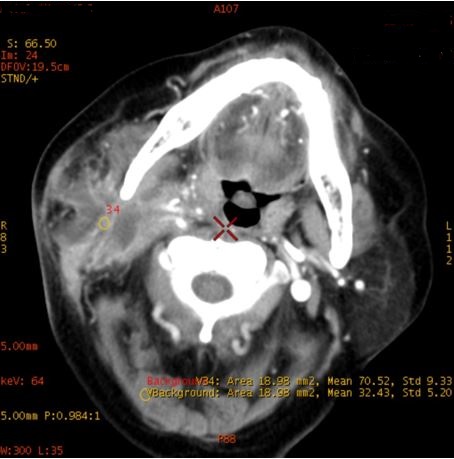

病例资料: 女,72岁,颈部肿胀就诊

扫描方案: GSI22, 375mA@0.7s/rot@0.984:1@SFOV Large body

对比剂注射方案: 300mgI/100ml,对比剂60ml,盐水30ml,流速3.0ml/s

CT印象 右侧颈部间隙感染

CNR:64keV 最佳单能对比噪声信号比成像

ROI 1 颈部间隙感染 ROI 2 正常腮腺内脂肪 ROI 3 受感染侵犯的脂肪间隙 ROI 4-5 双侧咀嚼肌